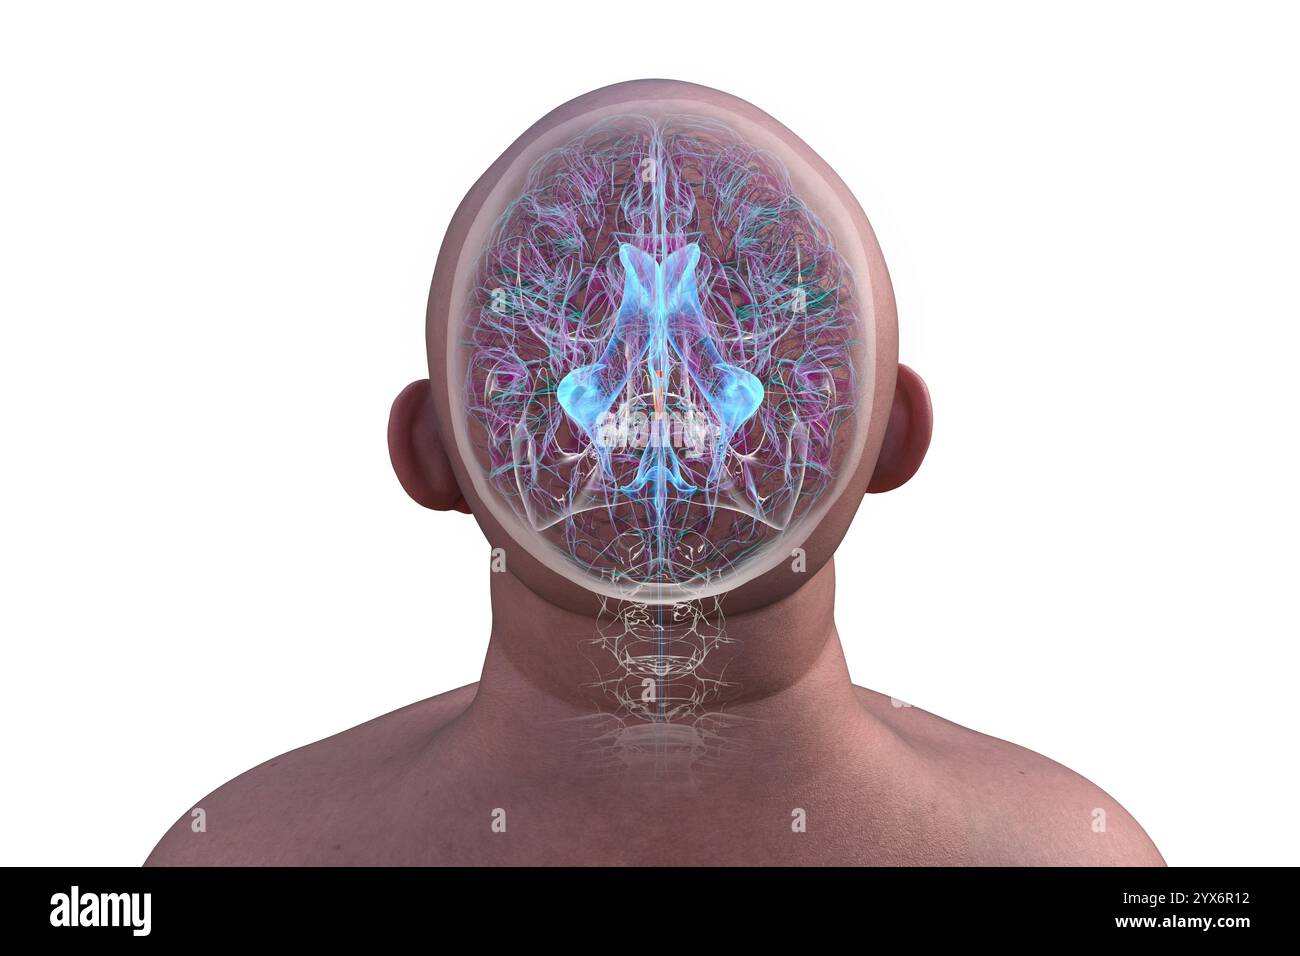

RF2YX6R0N–Computerdarstellung des menschlichen Gehirns mit orangefarbenem Aquädukt und grünem Ventrikelsystem, die den Liquorfluss (CSF) zeigen.

RF2YX6R0H–Computerdarstellung des menschlichen Gehirns mit orangefarbenem Aquädukt und grünem Ventrikelsystem, die den Liquorfluss (CSF) zeigen. Rückansicht.

RF2YYB740–Computerdarstellung des menschlichen Gehirns mit orangefarbenem Aquädukt und grünem Ventrikelsystem mit Liquorfluss. Rückansicht.